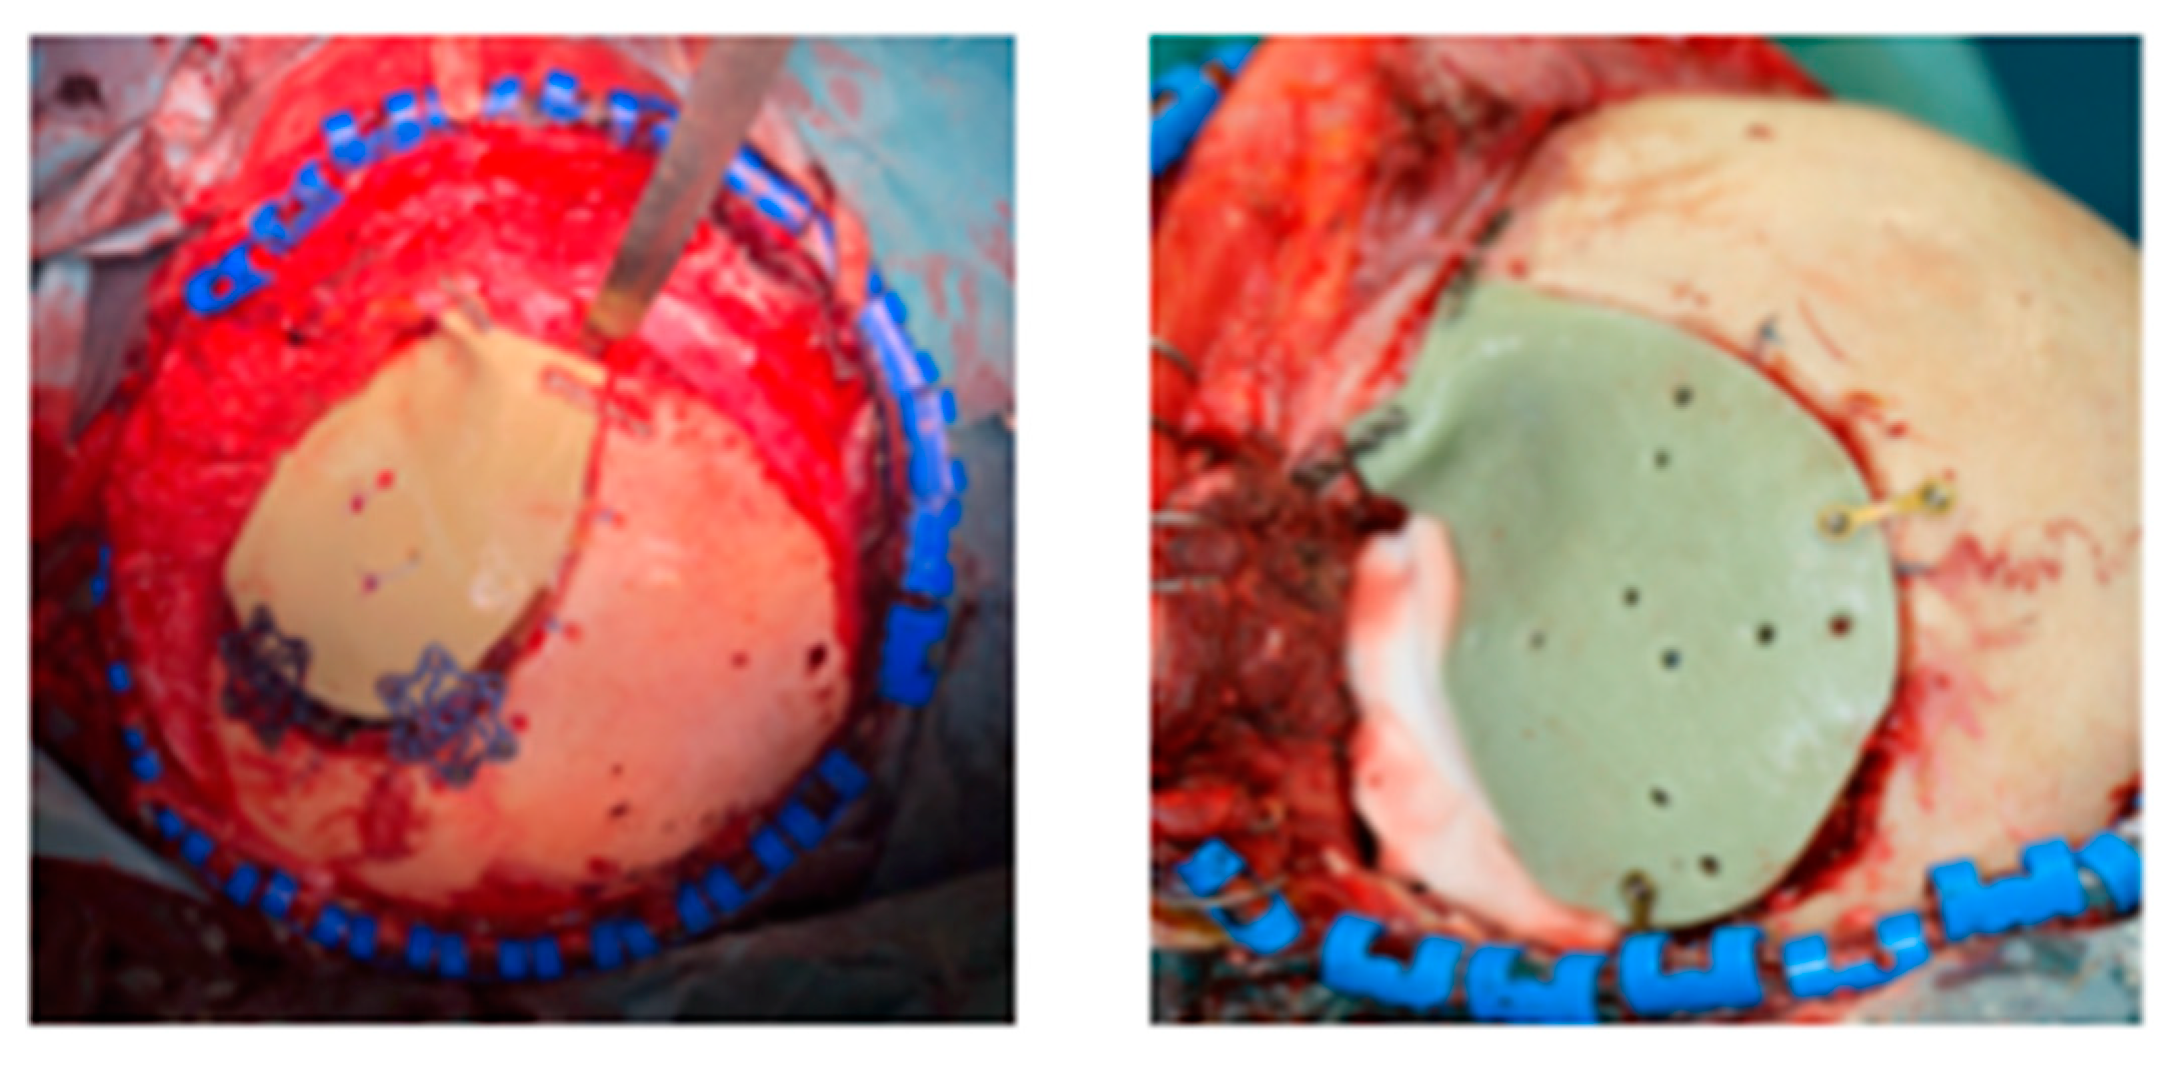

Figure 4.

Cranioplasty in PMMA with titanium fixation plates and screws.

The residual monomer, which could be coming-out from cold polymerization, is toxic. Further, the preparation of the malleable paste is an exothermic reaction (as high as 80 °C, 8–10 min), which could cause burn injuries like thermal necrosis and inflammation of the surrounding tissue [34]. Sometimes, to protect tissue from the heat, gauze saturated with saline solution are placed between the acrylic resin and the dura tissue. A very interesting scheme of PMMA paste preparation was published by Shah and collaborators [1]. PMMA is modelled by the surgeon to form a plate that then, through drilled holes, it is wired over the cranial defect. Inadequate cooling can cause damage to the brain tissue or dura in the surrounding area [18]. The surface texture ranges from smooth to coarse, with a degree of porosity ranging from 0% to 40% [42]. In respect to Ti, with an elastic modulus of approximatively 110 GPa, PMMA shows an elastic modulus of 3 GPa, with consequently less stress shielding and less loosening of fixation devices over time [42]. Examples of PMMA complication are fracture of cranioplasty and cranioplasty displacement, reported in Figure 5:

Figure 5.

(1) PMMA cranioplasty fractures; (2a) 3D and (2b) axial CT-scan of PMMA cranioplasty displacement.